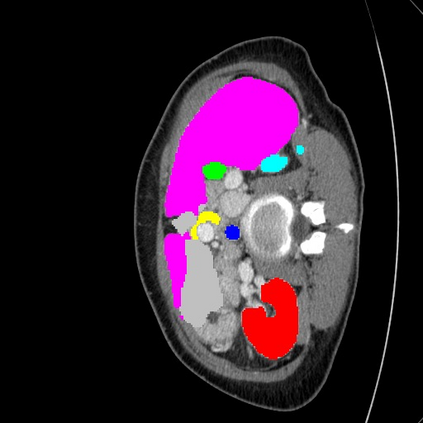

Transformers have made remarkable progress towards modeling long-range dependencies within the medical image analysis domain. However, current transformer-based models suffer from several disadvantages: (1) existing methods fail to capture the important features of the images due to the naive tokenization scheme; (2) the models suffer from information loss because they only consider single-scale feature representations; and (3) the segmentation label maps generated by the models are not accurate enough without considering rich semantic contexts and anatomical textures. In this work, we present CASTformer, a novel type of generative adversarial transformers, for 2D medical image segmentation. First, we take advantage of the pyramid structure to construct multi-scale representations and handle multi-scale variations. We then design a novel class-aware transformer module to better learn the discriminative regions of objects with semantic structures. Lastly, we utilize an adversarial training strategy that boosts segmentation accuracy and correspondingly allows a transformer-based discriminator to capture high-level semantically correlated contents and low-level anatomical features. Our experiments demonstrate that CASTformer dramatically outperforms previous state-of-the-art transformer-based approaches on three benchmarks, obtaining 2.54%-5.88% absolute improvements in Dice over previous models. Further qualitative experiments provide a more detailed picture of the model's inner workings, shed light on the challenges in improved transparency, and demonstrate that transfer learning can greatly improve performance and reduce the size of medical image datasets in training, making CASTformer a strong starting point for downstream medical image analysis tasks.